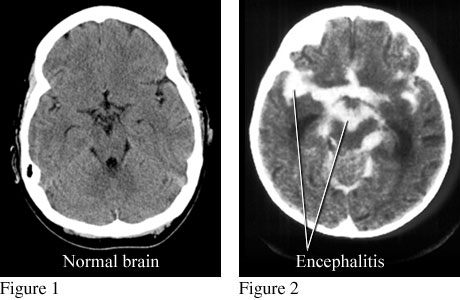

EncephalitisCourtesy of Paul Traughber, M.D., Boise,

Idaho. Figure 1 is a computed tomography (CT) scan of a normal brain. Figure

2 is a CT scan that shows an accumulation of contrast material in infected

areas and around the brain from encephalitis. ByHealthwise Staff Primary Medical ReviewerE. Gregory Thompson, MD - Internal Medicine Adam Husney, MD - Family Medicine Specialist Medical ReviewerChristine Hahn, MD - Epidemiology Current as ofMarch 3, 2017 Current as of: